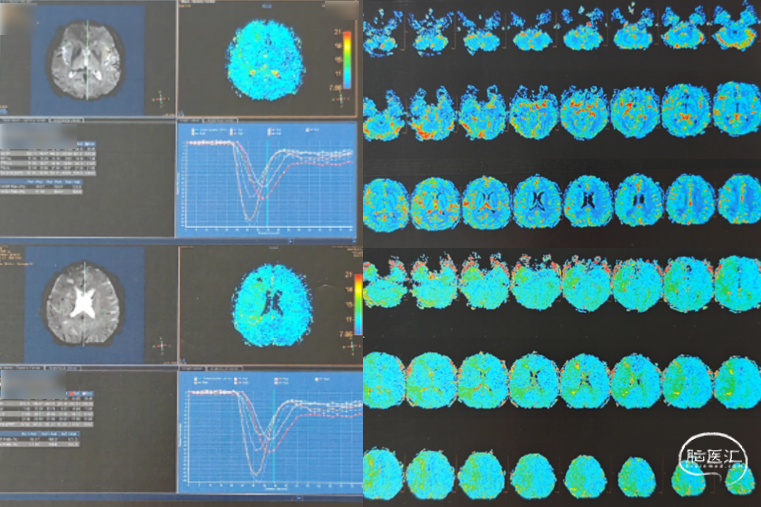

PWI(2024.11.07)

选对患者:中年男性,症状性颈内动脉非急性期闭塞。PWI示供血区明显缺血半暗带;手术指征明确。闭塞为B型,传统开通风险大,采用COSIS技术开通成功。